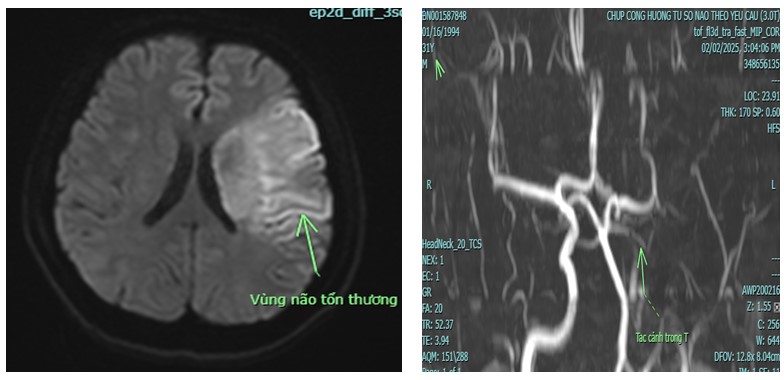

İnme Merkezi'ne kabul edildiğinde hasta bilinç bulanıklığı, aşırı ajite ve vücudunun sağ tarafında tamamen felç (kas gücü 0/5) halindeydi. Hastaneye sevk edilmeden önce yapılan konsültasyon nedeniyle hasta acil serviste hızla muayene edildi ve beyin 3.0 manyetik rezonans görüntüleme (MRG) istendi. Bu görüntüleme, sadece beyin damarlarını değil, aynı zamanda beyin perfüzyonunu da değerlendirme işlevi görüyordu. Hastanın beyin MR'ı, sol iç karotid arter tıkanıklığına bağlı beyin enfarktüsü görüntüsü gösterdi.

Sol internal karotid arter tıkanıklığına bağlı akut serebral enfarktüsün görüntüsü

Hasta Phu Tho Genel Hastanesi'ne 9. saatte (müdahalenin iskemik inme tedavisinde oldukça etkili olması için gereken zaman dilimi olan altın saati geçtikten sonra) sevk edilmiş olsa da, 3.0 manyetik rezonans görüntüleme ile serebral perfüzyon değerlendirmesi yapıldığında, doktorlar revaskülarizasyon müdahalesinin altın saat dışında yapılması durumunda bazı beyin hücre bölgelerinin kurtarılabileceğini ve durumun kötüleşmesini önleyebileceğini tespit ettiler. Bir diğer önemli faktör ise hastanın çok genç olmasıydı (31 yaşında), bu nedenle doktorlar geç müdahaleye karar verdiler.